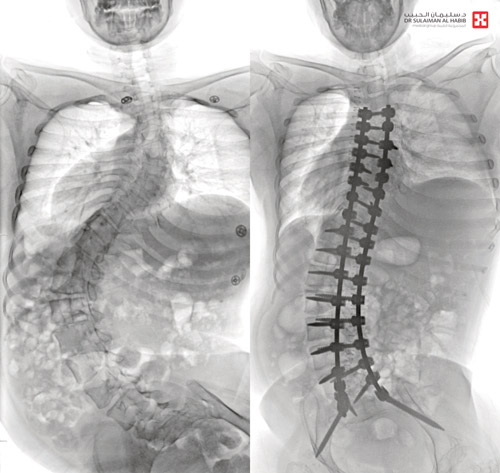

بفضل من الله تعالى، تمكن مستشفى الدكتور سليمان الحبيب بالقصيم من إجراء عملية ناجحة ومعقدة لسيدة من ذوي الإعاقة في الأربعين من العمر أعادت لها حياتها الطبيعية التي فقدتها نتيجة إصابتها بانحراف في العمود الفقري نتيجة حادث مروري. وعانت السيدة من جنف تجاوز «80» درجة في العمود الفقري مع ميلان كبير في الورك نتج عنه الكثير من الأعراض الحادة. ونجح الفريق الطبي الذي قاده د. صلاح الدين الخليفة استشاري جراحة العظام والعمود الفقري، ود. هاني الجهني استشاري جراحة المخ والأعصاب في إجراء العملية المعقدة التي أنهت آلام السيدة.

وقال د. خليفة أن السيدة راجعت المستشفى وهي بحالة صحية معقدة إذ كانت تجد صعوبة بالغة في الحركة والجلوس، وعدم القدرة على ممارسة حياتها إلا بمعاونة الأهل. وقد أظهرت الفحوصات أن لديها انحراف «جنف» عالٍ فوق «80» درجة وميلان كبير بالورك، وللحد من المضاعفات أجريت للسيدة عملية تم فيها تقويم العمود الفقري بعدد «30» من براغي التايتانيوم، وتثبيت ودمج الفقرات.

واستخدمت في العملية، التي استمرت 6 ساعات، أحدث الأجهزة التي ساهمت مع الكوادر الطبية عالية الكفاءة والتأهيل بالمستشفى ولله الحمد في إنجاحها.